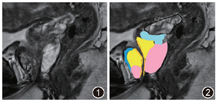

前列腺是腹膜后脏器,位于直肠前方和耻骨联合后方。前列腺自上而下分成3等分,即底部、中部和尖部。前列腺底部连接于膀胱颈部。尿道前列腺部进入前列腺底部的前表面。前列腺尖部位于泌尿生殖隔的上方,与肛提肌内侧面接触(图1,2)。前列腺体积随年龄增大而增大,20岁男性前列腺平均体积为11.5 ml,约为60岁男性前列腺体积的1/3。

前列腺尿道是前列腺的重要解剖参考点。前列腺尿道在中点,精阜分为近端尿道和远端尿道,平均成角35°。尿道周围腺体区由微小管和腺泡道组成。膜性尿道的长度为6~24 mm。前列腺尿道在T2WI中表现为高信号,被较低信号强度的尿道肌和尿道周围组织所包围(图1,2)。